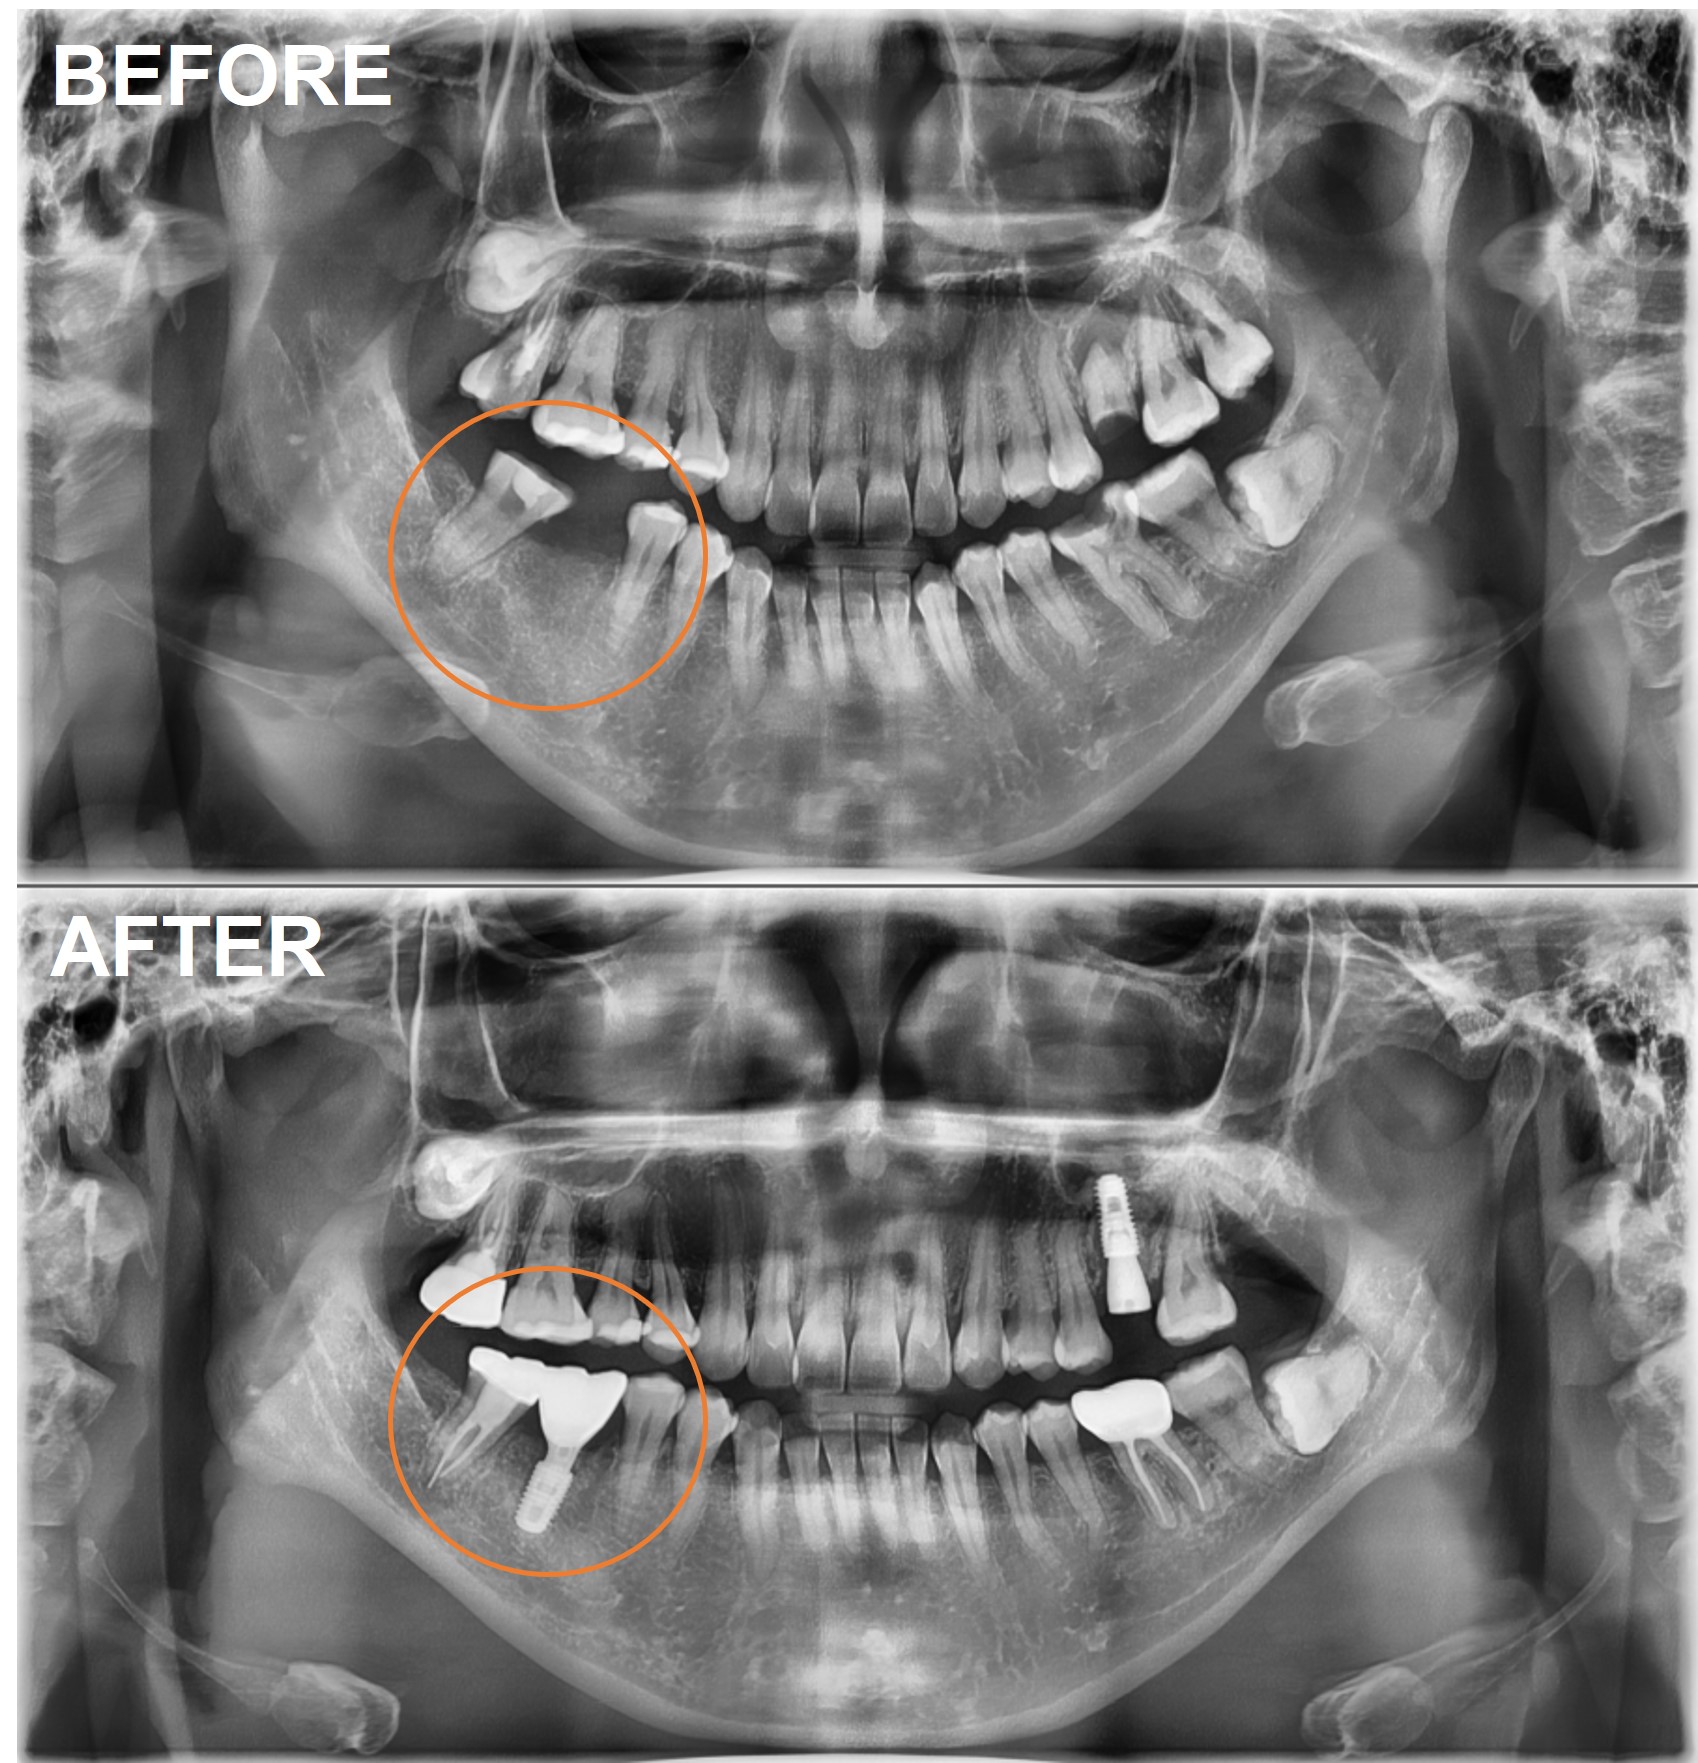

검단가온치과 임플란트 크라운 치료 전후 파노라마 X-RAY

검사부터 최종 보철까지 총 6단계로 진행되며, 일반적인 경우 전체 치료 기간은 약 3~5개월입니다.

1단계 검사 및 CT: 파노라마 촬영 후 필요 시 CT로 잇몸뼈 상태를 확인합니다.

2단계 발치·뼈이식 (필요 시): 케이스에 따라 발치나 뼈이식을 먼저 진행합니다.

3단계 임플란트 식립: 잇몸뼈에 인공 치근을 심는 수술입니다.

4단계 골유착 및 치유: 뼈와 임플란트가 단단히 결합되는 기간으로 약 2~4개월 소요됩니다.

5단계 지대주 및 크라운 보철: 임플란트와 크라운을 연결하는 지대주를 장착하고, 최종 인공 치아를 올립니다.

6단계 정기검진 및 유지관리: 3~6개월 주기로 정기검진과 구강위생 관리를 받습니다.